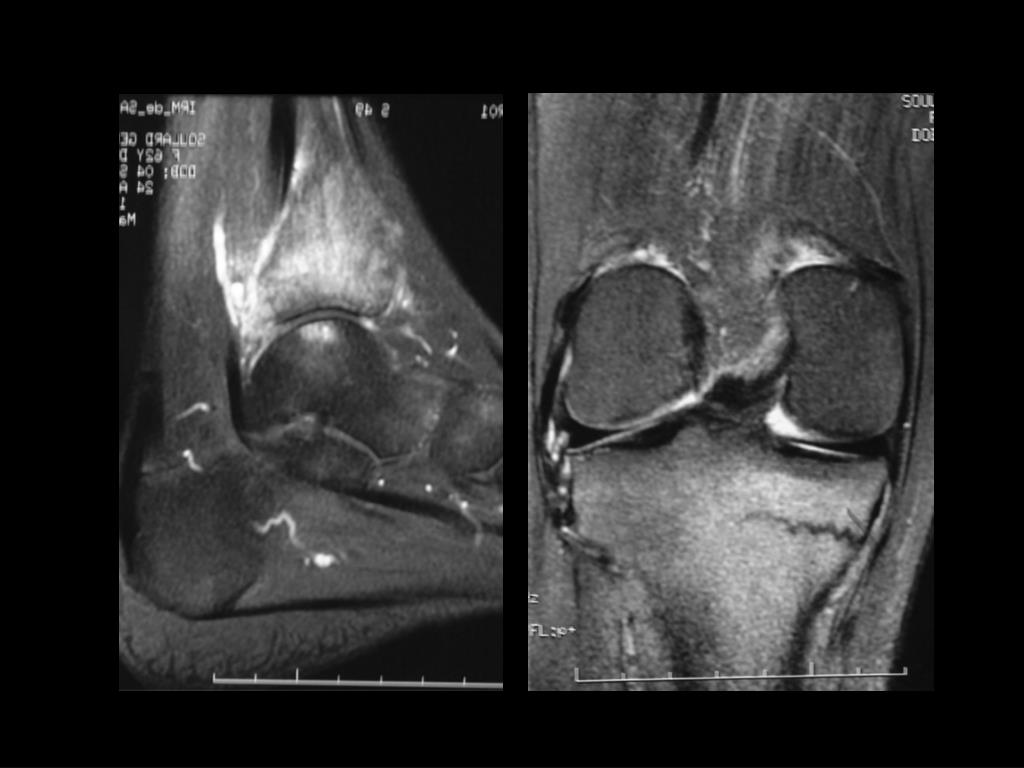

2. Mne 63 ans rachialgies inflammatoires résistantes aux AINS polyarthrite, syndrome inflammatoire IRM initiale

3. Nouvelle IRM ...